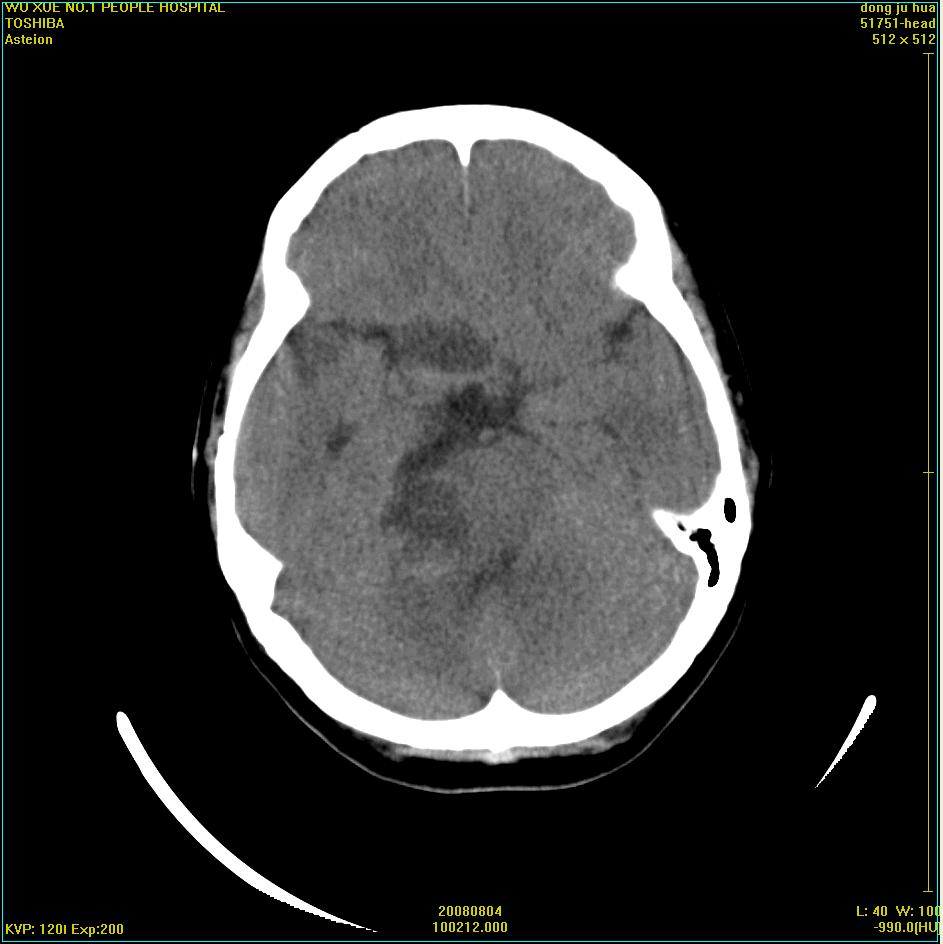

标题: CT15022:女,45岁。右侧桥小脑脚区三叉神经鞘膜瘤,已做手 [打印本页]

标题: CT15022:女,45岁。右侧桥小脑脚区三叉神经鞘膜瘤,已做手

患者,女,45岁。四年前在我院做ct诊断为右侧桥小脑脚区三叉神经鞘膜瘤,已做手术。今复杳。请大家看看

考虑三叉神经鞘膜瘤术后复发并瘤体内出血。

三叉神经鞘膜瘤术后复发并瘤体内出血

考虑慢性扩张性血肿吧!请大家再看看,发表高见!

四年前做的手术,为什么大家不考虑慢性颅内血肿呢?